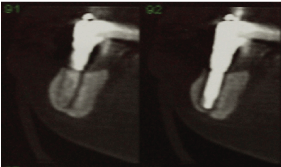

During the visit, an increase in volume was observed in the posterior region of the mandible on the right side and mobility in the region of the most distal implant, where it was impossible to diagnose whether the mobility was from the implant or resulting from the mandibular fracture (Figure 1). After the images were examined, a radiolucent line was observed beginning at the crest of the flap and continuing to the basal at the implant, characterizing a mandibular fracture without detachment of fragments. It was also possible to observe that this was a mandible with little bone height and the other implants revealed marginal bone loss with the exception of one (Figures 2 and 3).

Figure 3: Tomographic cuts of the distal implant where the mandibular fracture can be confirmed without detachment.